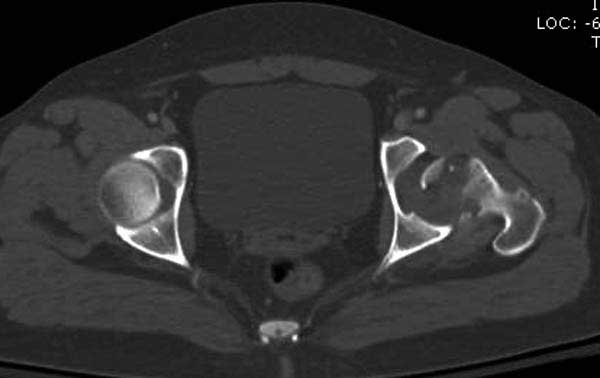

Женщина 28 лет, политравма.

По протоколу обследования больных с травмой сделаны все исследования и выставлен диагноз: разрыв печени и селезенки; множественные переломы ребер и лицевого черепа; стабильный перелом позвоночника, переломо-вывих головки левого бедра, перелом диафиза правого бедра, переломо-вывих правого тарана.